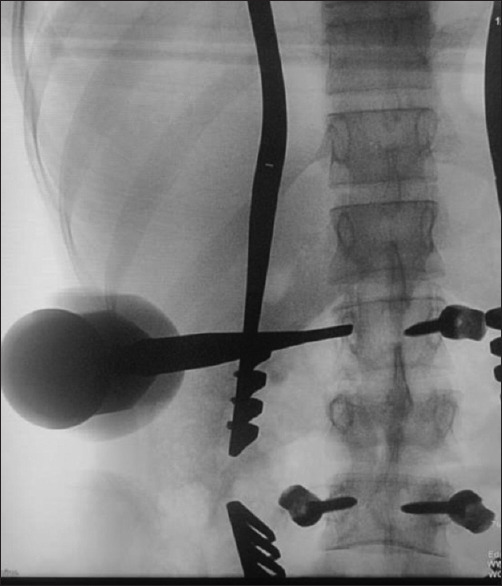

Results: In our study, we included 102 patients including 62 (60.7%) males and 40 (39.2%) females. More than half of patients were young in the age group of 20-50 years. Our study population had a varied etiology with 43.1% of patients having vertebral column instability due to trauma. The other etiologies were spondylolisthesis and lumbar canal stenosis (39.2%), Pott's spine (11.7%), tumors (2.9%), and osteoporotic fractures (2.9%). Majority of patients (44.1%) presented with lower backache with radiculopathy. All the transpedicular screws inserted were evaluated by C-arm to assess for screw fixation. In the first year of our study, an average of 4 anteroposterior (AP) and 4 lateral C-arm X-ray shots were taken per screw placement. In the next year, an average of 3 AP and 3 lateral shots and finally in the last year of our study only 2 AP and 2 lateral C-arm X-ray shots were taken per screw placement. Out of 650 screws placed, 4 screws were identified to cause breach with maximum breaches in the lumbar spine fixation. In dorsal spine fixation, there was 1 lateral breach at D10. In lumbar spine fixation, there were 3 breaches: two medial one each at L4 and L5 and one anterior at L2 level. The various complications include wound infection, temporary and permanent neurological deficit, screw breakage, screw misplacement, cerebrospinal fluid leaks, nonunion, and spinal epidural hematoma.